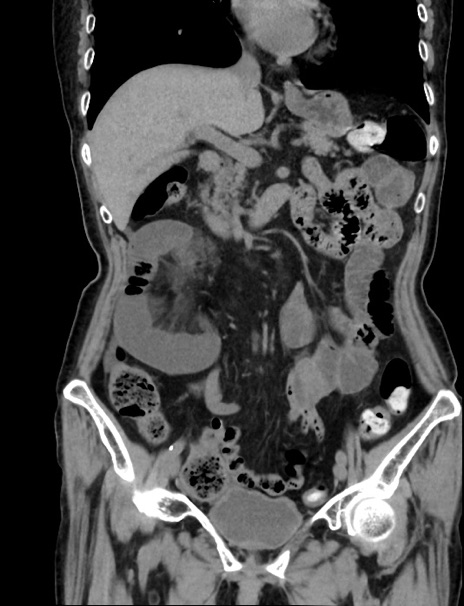

横断像